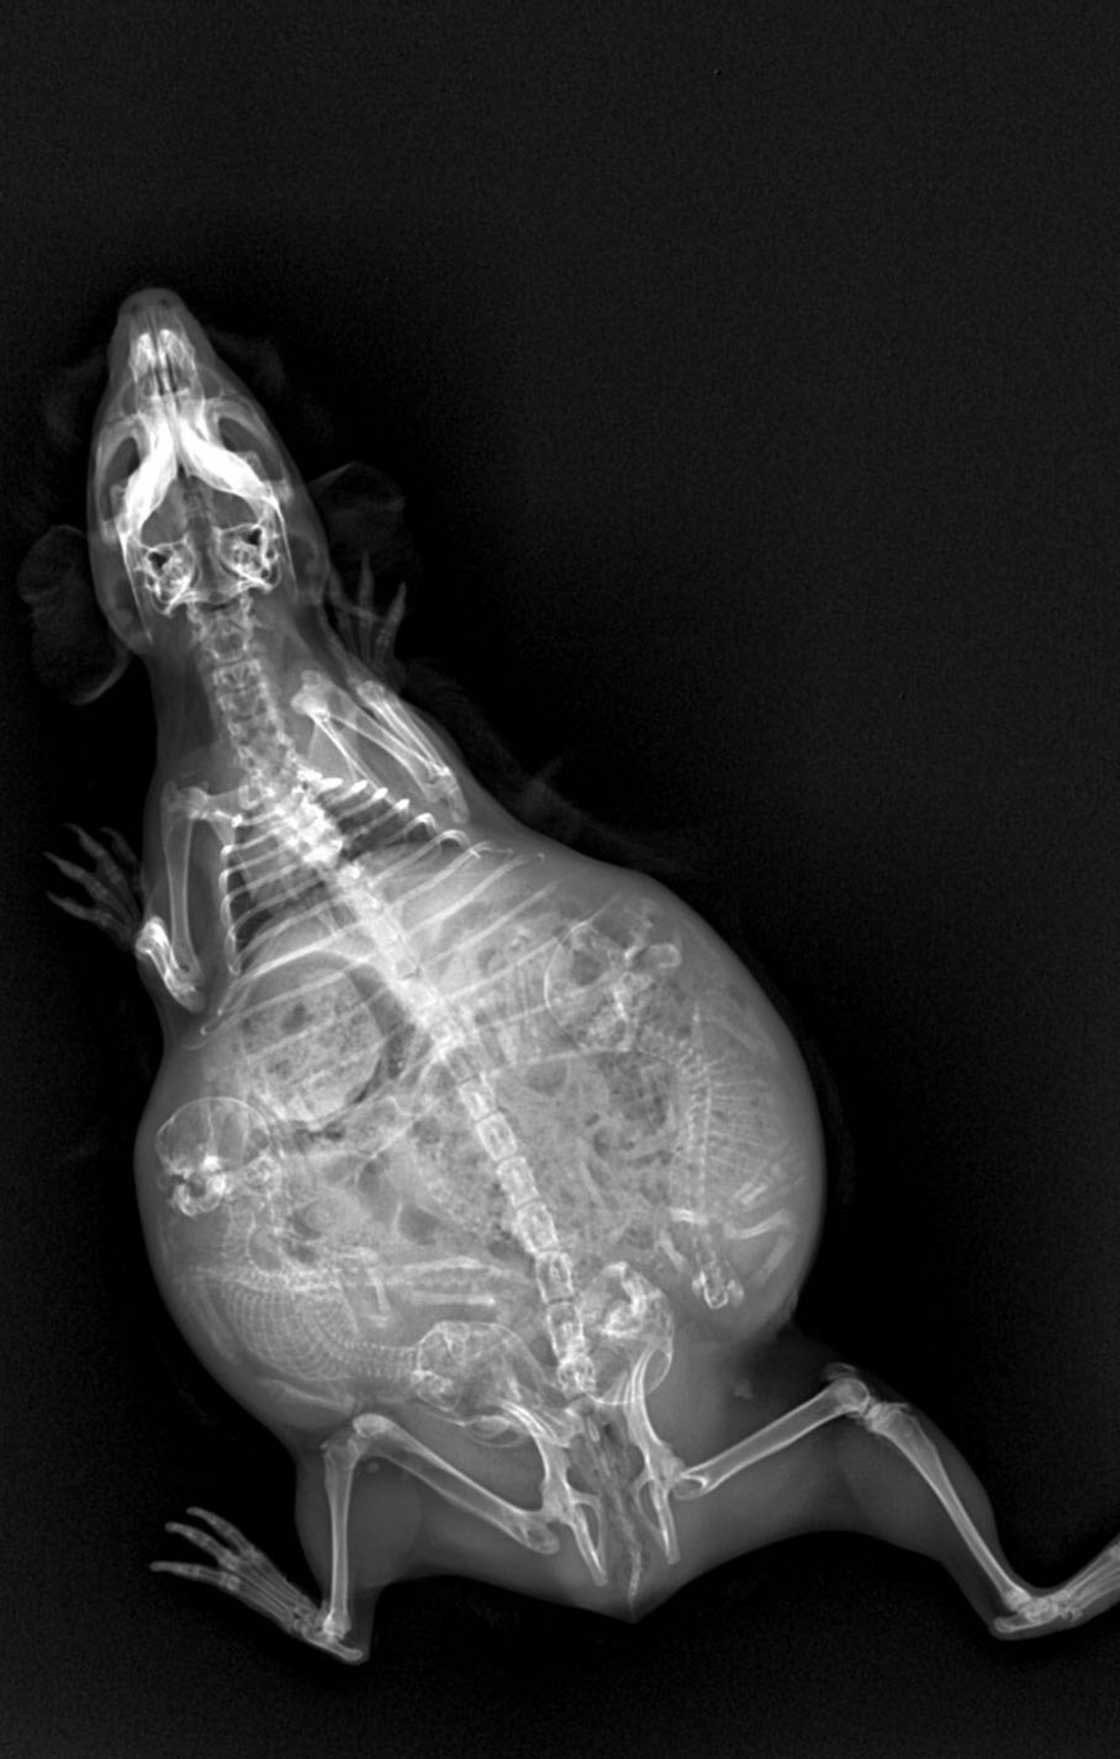

Беременная птичка киви

Дикие самки откладывают 1 яйцо примерно в 3-5 лет. Во время вынашивания яйца оно занимает около 20% всего тела птицы.

Это удивительная птица вынашивает яйцо в 6 раз больше положенного в соответствии с пропорциями её тела.